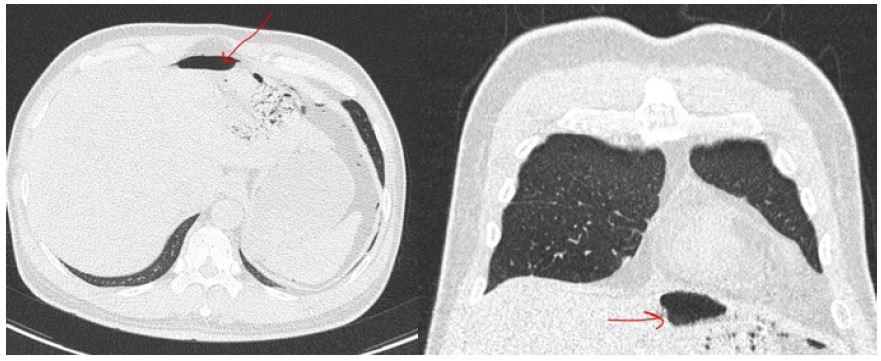

Figure 2: A and B showing gas forming liver abscess with perforation in soft tissue window C and D showing the liver abscess and the perforation in lung window.

General surgery was consulted to rule out perforated viscous and CT of the abdomen and pelvis without contrast was requested as he was having kidney injury, and the CT showed multiple, variable size, hypodense, non-enhancing focal lesions in the liver with pneumoperitoneum. The largest lesion was in the left lobe. It contained excessive air bubbles and its anterior and medial wall showed defects and subsequent air tracking into the upper peritoneal cavity. It measured about 68 x 63 mm with other smaller lesions were noted in the right lobe. These features were suggestive of multiple liver abscesses with perforation (Figure 2).